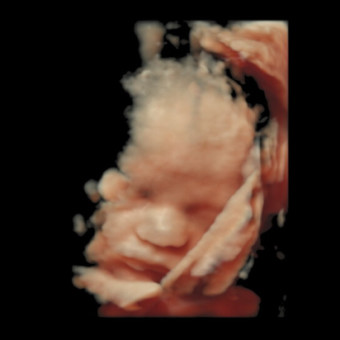

Baby Girl Varner Registry

Angela Varner

We are so grateful for gifts of any kind, thank you for showering us with love! Her nursery theme is "wildflower" - our little spring blossom!